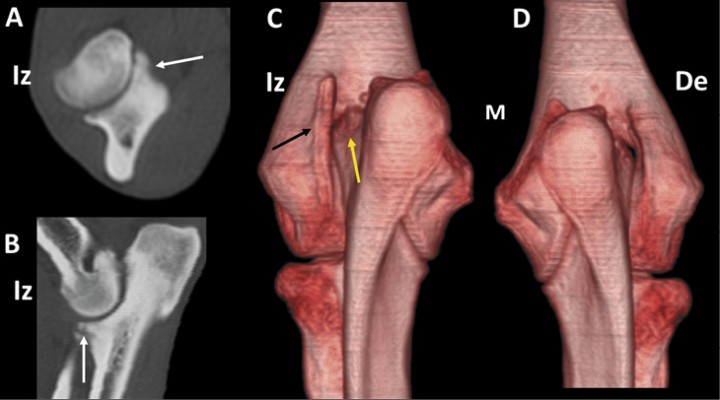

<p>Podenco macho de 42 meses con cojera bilateral por fragmentación de las apófisis coronoides medial de ambos codos. Planos transversal (<strong>A</strong>) y sagital (<strong>B</strong>) del codo izquierdo (Iz) que muestra fragmentación de la apófisis coronoides medial del cúbito (flechas blancas). Imágenes en 3D en vistas caudales de los codo izquierdo (<strong>C</strong>) y derecho (<strong>D</strong>). Existe una importante remodelación del epicóndilo lateral izquierdo (C) (flecha negra) acompañada de remodelación de la apófisis ancónea (flecha amarilla). Se muestra el codo derecho (De) para comparación.</p>

Podenco macho de 42 meses con cojera bilateral por fragmentación de las apófisis coronoides medial de ambos codos. Planos transversal (A) y sagital (B) del codo izquierdo (Iz) que muestra fragmentación de la apófisis coronoides medial del cúbito (flechas blancas). Imágenes en 3D en vistas caudales de los codo izquierdo (C) y derecho (D). Existe una importante remodelación del epicóndilo lateral izquierdo (C) (flecha negra) acompañada de remodelación de la apófisis ancónea (flecha amarilla). Se muestra el codo derecho (De) para comparación.